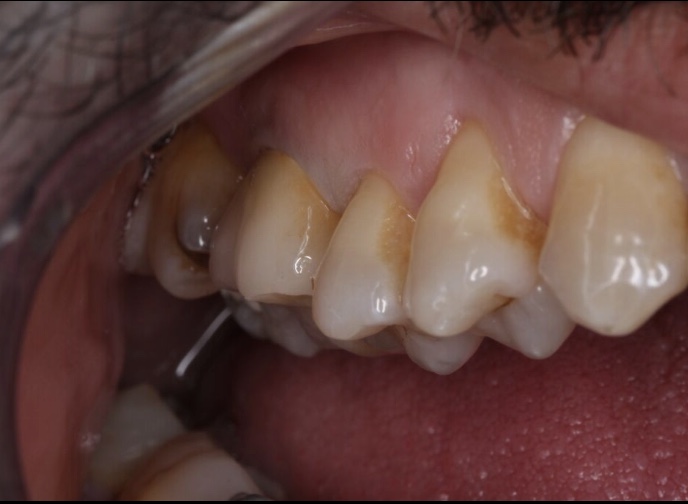

Nos réalisations : Conjointe

Céramique sur Zircone

Biocompatible elle est garante d’une excellente intégration gingivale.